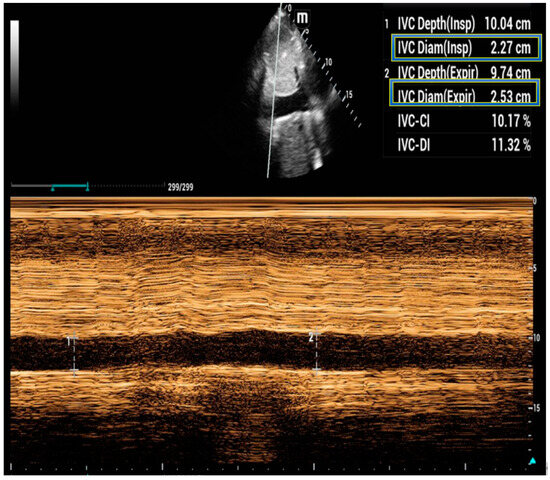

5. Inferior Vena Cava Ultrasound

- Brennan, J.M.; Blair, J.E.; Goonewardena, S.; Ronan, A.; Shah, D.; Vasaiwala, S.; Kirkpatrick, J.N.; Spencer, K.T. Reappraisal of the use of inferior vena cava for estimating right atrial pressure. J. Am. Soc. Echocardiogr. 2007, 20, 857–861. [Google Scholar] [CrossRef]

- Lang, R.M.; Badano, L.P.; Mor-Avi, V.; Afilalo, J.; Armstrong, A.; Ernande, L.; Flachskampf, F.A.; Foster, E.; Goldstein, S.A.; Kuznetsova, T.; et al. Recommendations for cardiac chamber quantification by echocardiography in adults: An update from the American Society of Echocardiography and the European Association of Cardiovascular Imaging. J. Am. Soc. Echocardiogr. 2015, 16, 233–271. [Google Scholar]

- Nakao, S.; Come, P.C.; McKay, R.G.; Ransil, B.J. Effects of positional changes on inferior vena caval size and dynamics and correlations with right-sided cardiac pressure. Am. J. Cardiol. 1987, 59, 125–132. [Google Scholar] [CrossRef] [PubMed]

- Rudski, L.G.; Lai, W.W.; Afilalo, J.; Hua, L.; Handschumacher, M.D.; Chandrasekaran, K.; Solomon, S.D.; Louie, E.K.; Schiller, N.B. Guidelines for the echocardiographic assessment of the right heart in adults: A report from the American Society of Echocardiography endorsed by the European Association of Echocardiography, a registered branch of the European Society of Cardiology, and the Canadian Society of Echocardiography. J. Am. Soc. Echocardiogr. 2010, 23, 685–713; quiz 686–688. [Google Scholar]

- La Via, L.; Astuto, M.; Dezio, V.; Muscara, L.; Palella, S.; Zawadka, M.; Vignon, P.; Sanfilippo, F. Agreement between subcostal and transhepatic longitudinal imaging of the inferior vena cava for the evaluation of fluid responsiveness: A systematic review. J. Crit. Care 2022, 71, 154108. [Google Scholar] [CrossRef]

- Sanfilippo, F.; La Via, L.; Dezio, V.; Santonocito, C.; Amelio, P.; Genoese, G.; Astuto, M.; Noto, A. Assessment of the inferior vena cava collapsibility from subcostal and trans-hepatic imaging using both M-mode or artificial intelligence: A prospective study on healthy volunteers. Intensive Care Med. Exp. 2023, 11, 15. [Google Scholar] [CrossRef] [PubMed]

- Sanfilippo, F.; La Via, L.; Dezio, V.; Amelio, P.; Genoese, G.; Franchi, F.; Messina, A.; Robba, C.; Noto, A. Inferior vena cava distensibility from subcostal and trans-hepatic imaging using both M-mode or artificial intelligence: A prospective study on mechanically ventilated patients. Intensive Care Med. Exp. 2023, 11, 40. [Google Scholar] [CrossRef]

- Wallace, D.J.; Allison, M.; Stone, M.B. Inferior vena cava percentage collapse during respiration is affected by the sampling location: An ultrasound study in healthy volunteers. Acad. Emerg. Med. 2010, 17, 96–99. [Google Scholar] [CrossRef] [PubMed]

- Feissel, M.; Michard, F.; Faller, J.P.; Teboul, J.L. The respiratory variation in inferior vena cava diameter as a guide to fluid therapy. Intensive Care Med. 2004, 30, 1834–1837. [Google Scholar] [CrossRef]

- Barbier, C.; Loubieres, Y.; Schmit, C.; Hayon, J.; Ricome, J.L.; Jardin, F.; Vieillard-Baron, A. Respiratory changes in inferior vena cava diameter are helpful in predicting fluid responsiveness in ventilated septic patients. Intensive Care Med. 2004, 30, 1740–1746. [Google Scholar] [CrossRef]

- Besli, F.; Kecebas, M.; Caliskan, S.; Dereli, S.; Baran, I.; Turker, Y. The utility of inferior vena cava diameter and the degree of inspiratory collapse in patients with systolic heart failure. Am. J. Emerg. Med. 2015, 33, 653–657. [Google Scholar] [CrossRef]

- Pellicori, P.; Carubelli, V.; Zhang, J.; Castiello, T.; Sherwi, N.; Clark, A.L.; Cleland, J.G. IVC diameter in patients with chronic heart failure: Relationships and prognostic significance. JACC Cardiovasc. Imaging 2013, 6, 16–28. [Google Scholar] [CrossRef] [PubMed]

- Khandwalla, R.M.; Birkeland, K.T.; Zimmer, R.; Henry, T.D.; Nazarian, R.; Sudan, M.; Mirocha, J.; Cha, J.; Kedan, I. Usefulness of Serial Measurements of Inferior Vena Cava Diameter by Vscan(TM) to Identify Patients With Heart Failure at High Risk of Hospitalization. Am. J. Cardiol. 2017, 119, 1631–1636. [Google Scholar] [CrossRef] [PubMed]

- Cubo-Romano, P.; Torres-Macho, J.; Soni, N.J.; Reyes, L.F.; Rodriguez-Almodovar, A.; Fernandez-Alonso, J.M.; Gonzalez-Davia, R.; Casas-Rojo, J.M.; Restrepo, M.I.; de Casasola, G.G. Admission inferior vena cava measurements are associated with mortality after hospitalization for acute decompensated heart failure. J. Hosp. Med. 2016, 11, 778–784. [Google Scholar] [CrossRef]

- Simonson, J.S.; Schiller, N.B. Sonospirometry: A new method for noninvasive estimation of mean right atrial pressure based on two-dimensional echographic measurements of the inferior vena cava during measured inspiration. J. Am. Coll. Cardiol. 1988, 11, 557–564. [Google Scholar] [CrossRef] [PubMed]

- Goldhammer, E.; Mesnick, N.; Abinader, E.G.; Sagiv, M. Dilated inferior vena cava: A common echocardiographic finding in highly trained elite athletes. J. Am. Soc. Echocardiogr. 1999, 12, 988–993. [Google Scholar] [CrossRef]